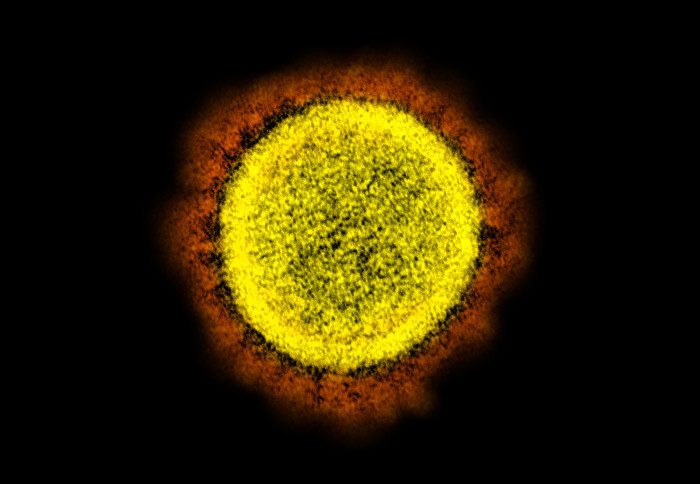

Compounds which bind to the spike protein block antibodies from neutralising SARS-CoV-2

In the study, researchers at the Crick were involved in the development of tests that see if a person has been exposed to the virus, and discovered that the SARS-CoV-2 spike protein strongly binds to biliverdin, giving the proteins an unusual green colouration.